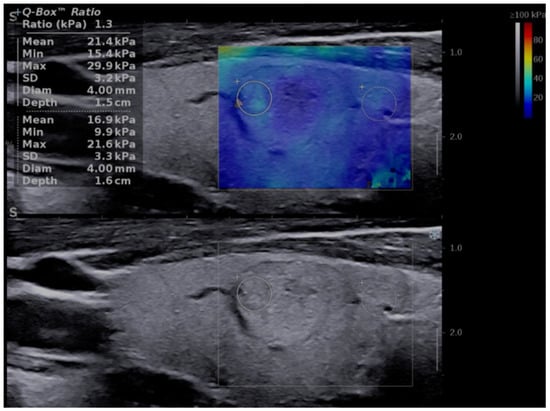

For the image acquisition, the box was adjusted to include the entire lesion. To acquire a stable, reliable elastogram, the examiner held the probe still for about 5 s and avoided applying external pressure. The machine does not provide a quality measure, so an experimented operator should perform the evaluation and avoid obtaining images with obvious compression artifacts such as “finger-like” artifacts or images with a completely red image (corresponding to high stiffness) []. Images lacking an SWE signal were also considered inadequate. The ROI was placed in the stiffest part of the nodule. The evaluation was uniform, and 5 values were registered for each lesion in longitudinal scans. The mean of the 5 measurements was considered in the analysis of the Max and Mean elasticity index (EI), measured in kPa. The QBox ratio was determined by comparing two ROIs, one in the stiffest displayed zone (without including obvious artifacts or calcifications inside the ROI) and one in the adjacent thyroid parenchyma or surrounding muscle, both placed at approximately the same depth, as shown in Figure 1. The diameter of the ROIs was set between 2–4 mm. Increased stiffness, documented by SWE evaluation, was considered as a high-risk parameter [,,,,].

Figure 1.

Transverse US scan displaying a soft thyroid nodule in the two-dimensional shear-wave elastography (2D-SWE) evaluation, first image (up): Mean elasticity index (EI) = 21.4 kPa, nodule-to-parenchyma QBox ratio = 1.3; and in the greyscale (2B) evaluation, second image (down): low-risk, isoechoic solid nodule, with a thin halo, well-defined borders, and no features of high risk.